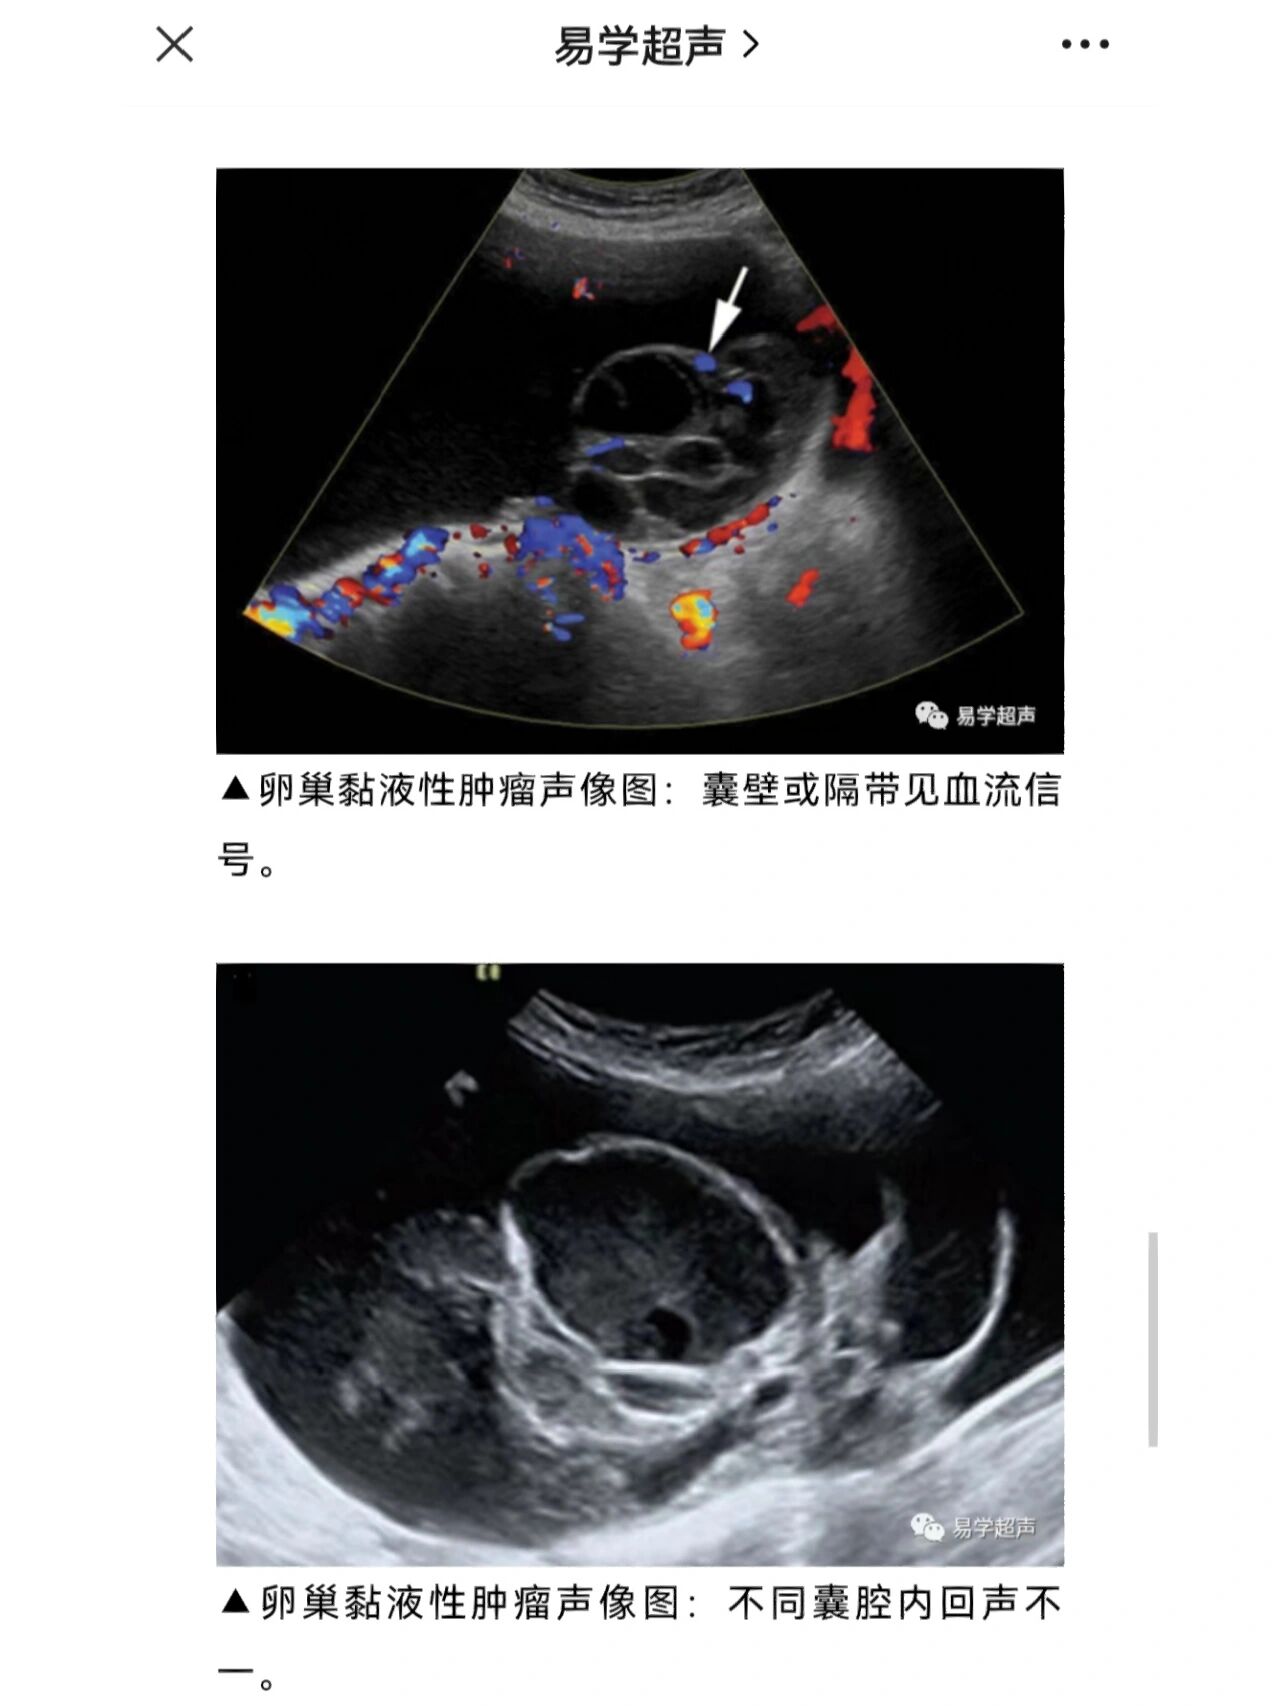

超声笔记-卵巢囊腺瘤 卵巢囊腺瘤包括浆液性和粘液性,浆液性更多见

图片尺寸1280x1706